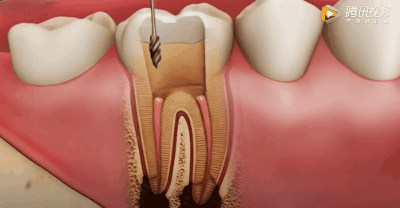

各种粗细型号的根管扩锉针

用根管器械在牙髓上做活塞运动

将坏的牙髓清理干净。目的是去净根管壁上的感染物,通过根管器械的切削作用去除感染的牙本质并清理根管壁细菌以利于根管充填。

用银针锉去除牙髓

同时清洗移除牙髓残质及细菌。根管冲洗的目的是清除微生物、冲掉残渣,润滑根管器械和溶解有机残渣。然后,再进行根管消毒,使根管内达到无菌状态。